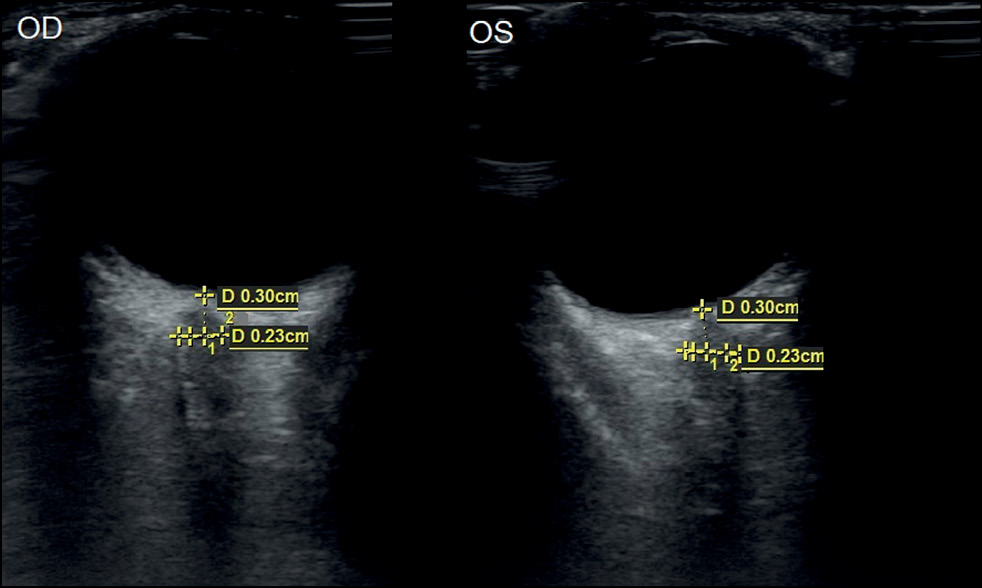

Анализ акустических биометрических параметров зрительного нерва в орбите у 50 здоровых детей (100 глаз) в группе контроля показал, что средние значения толщины нерва составили в 1-й группе 3,78±0,1 мм, во 2-й группе — 4,26±0,06 мм и в 3-й группе — 4,19±0,09 мм (рис. 1, 2). Сравнительная оценка параметров толщины зрительного нерва в разных возрастных группах показала статистически достоверное увеличение средних значений ТОЗН с возрастом ребенка (р <0,05) (табл. 1).

Рис. 2. Эхограмма зрительных нервов в норме у девочки в возрасте 10 лет. Биометрические показатели ретробульбарного отдела зрительного нерва правого (OD) и левого (OS) глаза.

Fig. 2. Echogram of the optic nerves of a healthy girl aged 10 years and biometric data of the retrobulbar optic nerve of the right (OD) and left (OS) eyes.